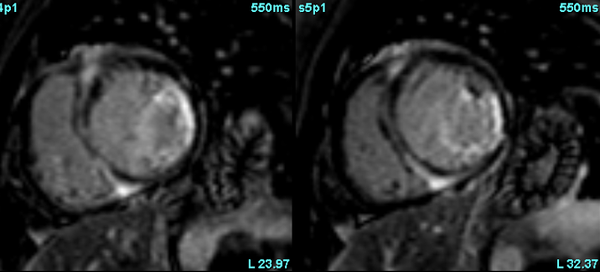

Not in Sync anymore..!

A common clinical presentation of LBBB induced cardiomyopathy is described in this post. It is always dilemma that if LBBB is cause or effect of dilated cardiomyopathy. However CMR can help in differentiating it from other causes and also in predicting response to device therapy. Utilise CMR to the fullest.